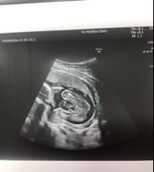

ขอดูภาพอัลตราซาวน์ หน่อยค่ะ ของเรา ทีมลูกสาวค่ะ

11 สิงหาค่ะ บ้านนี้ได้ลูกสาวววว🥰🥰